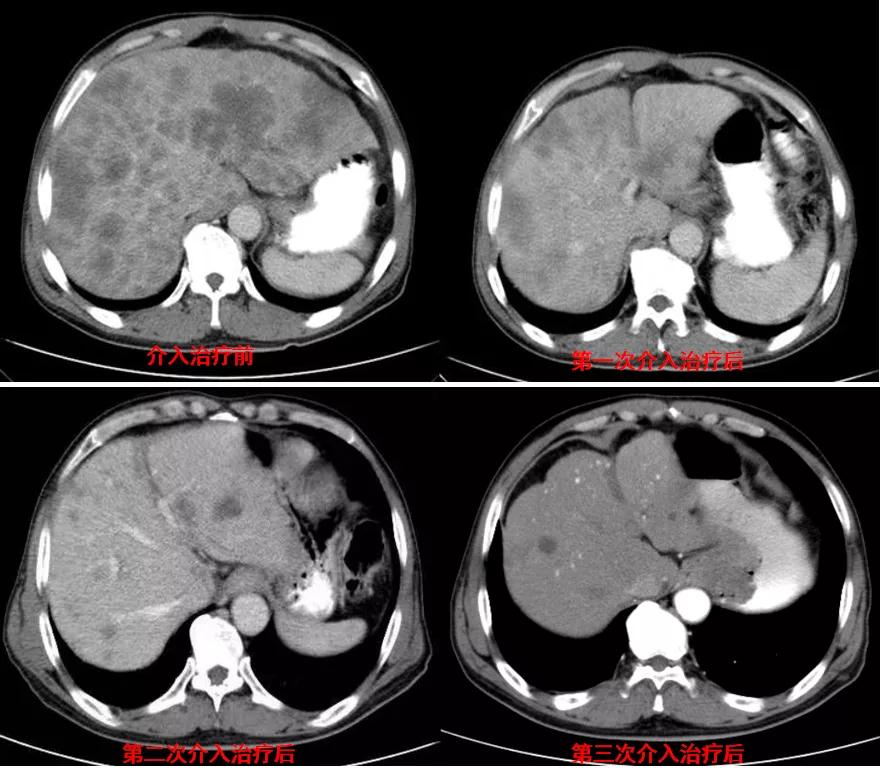

诊治经过:2020年11月25日患者行经皮动脉化疗灌注栓塞术(铂类+氟尿嘧啶);2020年11月30日免疫组化及基因检测结果为:ERBB-2扩增(9倍),VEGFR未突变,MSI微卫星低度不稳定,错配修复蛋白部分缺失(dMMR),MSH2(+弱),MLH1(-),MSH6(+),PMS2(-),CDX2(-),Villin(+),CK8/18(+),Ki67(5%+),CD56(-),Syn(-),CgA(-);患者为HER2阳性,患者肝脏病灶很多,残余正常肝脏体积小,需要寻找对肝功能影响小且抗瘤效果明显的治疗,因此联合吡咯替尼进行系统治疗。2020年12月14日复查结果提示肝脏病灶明显缩小(PR)。结果见图2。

图2